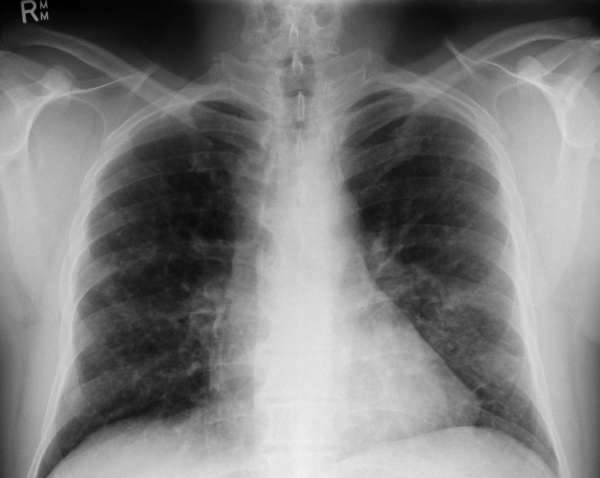

Рентгенография легких. Диффузные двусторонние узловые затемнения и небольшие кисты в верхней и средней доле

- Инструментальные исследования. При рентгенографии скелета находят очаги деструкции и остеолизиса, особенно выраженные в плоских костях черепа и длинных трубчатых костях. На рентгенограмме органов грудной клетки видны двусторонние мелкоочаговые затемнения (узелки, буллы), усиление легочного рисунка. Для более точной визуализации легочной ткани назначается компьютерная томография легких высокого разрешения, позволяющая определить их ячеистую деформацию. Результаты измерения функции внешнего дыхания (спирографии) показывают ухудшение диффузионной емкости легких.